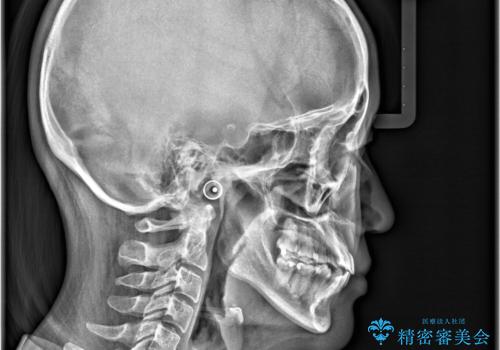

- 「歯のでこぼこを治したい」を主訴に来院された患者様です。 上下ともに、歯のでこぼこが強く、上下左右4の抜歯をし、ワイヤー矯正で治療を行いました。

かなり綺麗に並ぶ事ができ大変満足していただけました。

叢生量がかなり多かったのですが、歯肉退縮も失活歯も無くとても綺麗な歯並びになりました。

歯のでこぼこは、歯周病や虫歯のリスクも、とても高いので、見た目のみならず、将来の歯の寿命自体もかなり伸ばす事が出来た治療でした。